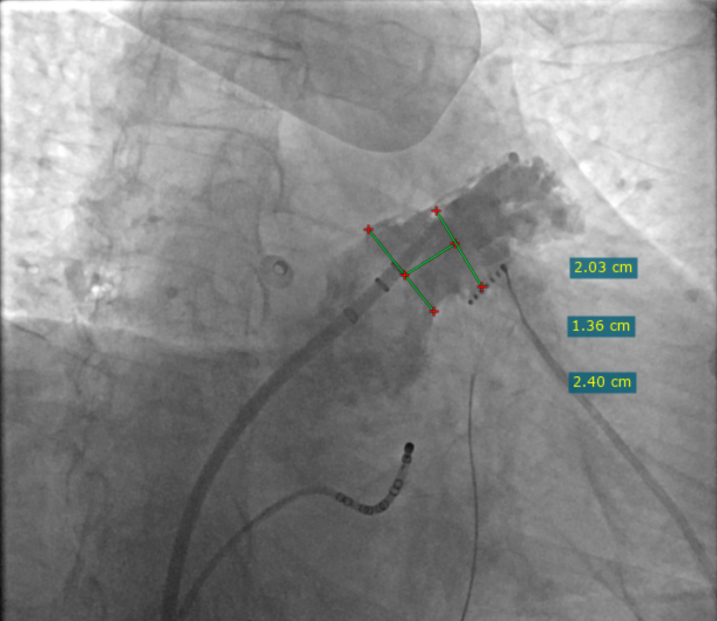

RAO 30° CAUD 20°测量锚定区:20.3mm;封堵区:24.0mm。

RAO 30° CAUD 20°造影

选择LAMax LAAC® 2430 Normal型号左心耳封堵器。